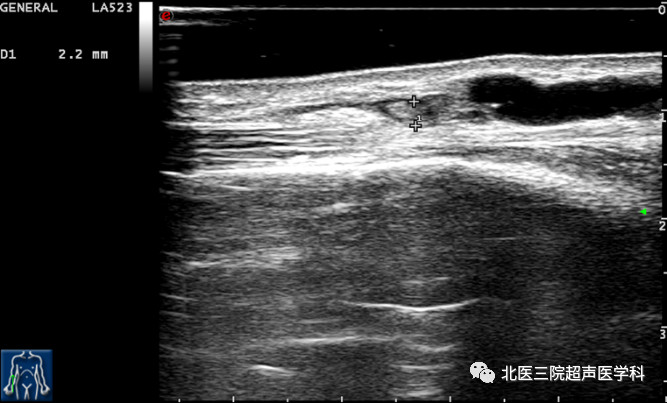

34岁男患,AVF3个月,近期开始穿刺,偶尔机器报警。超声证实头静脉主干闭塞。